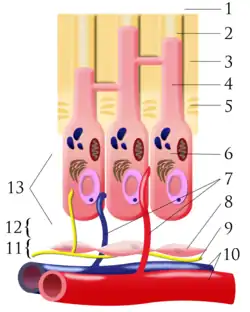

When dental caries is removed from a tooth, all or most of the infected and softened enamel and dentin are removed. This can lead to the pulp of the tooth either being exposed or nearly exposed.[1] To prevent the pulp from deteriorating when a dental restoration gets near the pulp, the dentist will place a small amount of a sedative dressing, such as calcium hydroxide or mineral trioxide aggregate (MTA). These materials protect the pulp from noxious agents (heat, cold, bacteria) and stimulate the cell-rich zone of the pulp to lay down a bridge of reparative dentin. Dentin formation usually starts within 30 days of the pulp capping (there can be a delay in onset of dentin formation if the odontoblasts of the pulp are injured during cavity removal) and is largely completed by 130 days.[2]: 491–494

Indirect

In 1938, Bodecker introduced the stepwise caries excavation (SWE) technique for treatment of teeth with deep caries for preservation of pulp vitality.[6] This technique is used when most of the decay has been removed from a deep cavity, but some softened dentin and decay remains over the pulp chamber that if removed would expose the pulp and trigger irreversible pulpitis. Instead, the dentist intentionally leaves the softened dentin or decay in place, and uses a layer of protective temporary material which promotes remineralization of the softened dentin over the pulp and the laying down of new layers of tertiary dentin in the pulp chamber. The color of the carious lesion changes from light brown to dark brown, the consistency goes from soft and wet to hard and dry so that Streptococcus mutans and Lactobacilli have been significantly reduced to a limited number or even zero viable organisms and the radiographs show no change or even a decrease in the radiolucent zone.[7] A temporary filling is used to keep the material in place, and about six months later, the cavity is re-opened and hopefully there is now enough sound dentin over the pulp (a "dentin bridge") that any residual softened dentin can be removed and a permanent filling can be placed. This method is also called "stepwise caries removal."[4][8] The difficulty with this technique is estimating how rapid the carious process has been, how much tertiary dentin has been formed and knowing exactly when to stop excavating to avoid pulp exposure.[9]

Calcium hydroxide (Ca(OH)2) is an organo-metallic cement that was introduced into dentistry in the early twentieth century[11] and there have since been many advantages to this material described in much of the available literature. Ca(OH)2 has a high antimicrobial activity which has been shown to be outstanding.[12][13] In one experiment conducted by Stuart et al. (1991), bacteria-inoculated root canals of extracted human teeth were treated with Ca(OH)2 for one hour against a control group with no treatment and the results yielded 64–100% reductions in all viable bacteria.[12] Ca(OH)2 also has a high pH and high solubility; thus, it readily leaches into the surrounding tissues.[14] This alkaline environment created around the cement has been suggested to give beneficial irritancy to pulpal tissues and stimulates dentin regeneration. One study further demonstrated that Ca(OH)2 causes release of growth factors TGF-B1 and bioactive molecules from the dentin matrix which induces the formation of dentin bridges.[15]

Ca(OH)2 does, however, have significant disadvantages. The set cement has low compressive strength and cannot withstand or support condensation of a restoration.[14][16] It is thus good practice to place a stronger separate lining material (e.g. glass ionomer or resin-modified glass ionomer) over Ca(OH)2 before packing the final restorative material.[10] Ca(OH)2 cement is not adhesive to tooth tissues and thus does not provide a coronal seal.[10] In pulp perfusion studies, Ca(OH)2 has shown to insufficiently seal all dentinal tubules, and presence of tunnel defects (patent communications within reparative dentin connecting pulp and exposure sites) indicate a potential for microleakage when Ca(OH)2 is used.[14][17] It is suggested that an adhesive coronal restoration be used above the Ca(OH)2 lining to provide adequate coronal seal. Because of its many advantageous properties and long-standing success in clinical use, it has been used as a control material in multiple experiments with pulp capping agents over the years[18][19] and is considered the gold standard dental material for direct pulp capping to date.[20]